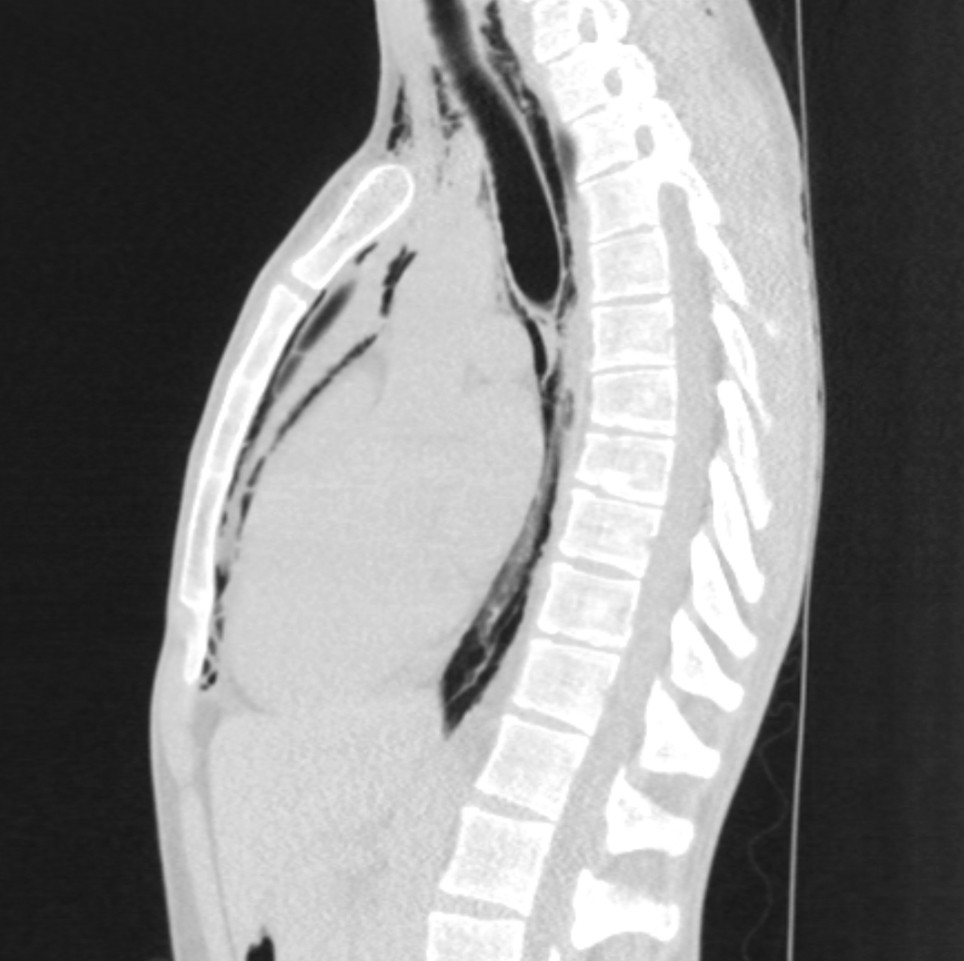

The chest x-ray shown is of a man in his twenties who experienced acute chest pain with accompanying dyspnoea while resting. The pain radiated to both shoulders and to the back, and was exacerbated by inspiration. He had stable vital parameters and blood tests were normal.

The chest x-ray showed air in the soft tissue of the neck and bilaterally in the supraclavicular region, along the trachea, heart, and along the aortic contour laterally. A thoracic CT without intravenous contrast confirmed pneumomediastinum and excluded pneumothorax. At clinical examination three weeks later the patient no longer had symptoms, and chest x-ray showed complete regression of the pneumomediastinum.